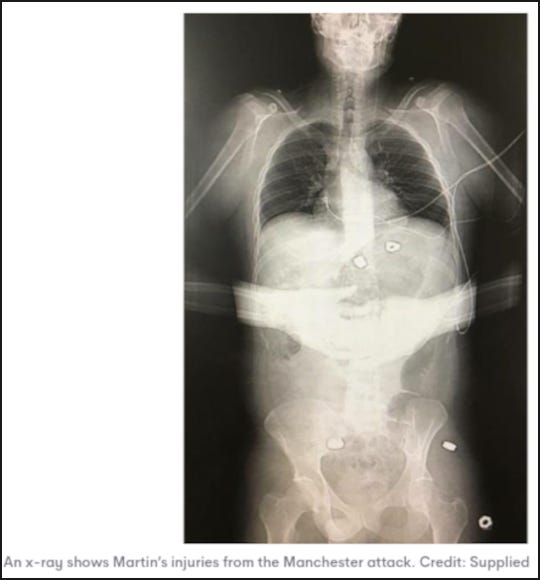

Sanders moves on to debunk the x-ray, also supplied by Hibbert to the legacy media, which Hall has questioned. Hall reports that he was contacted by two medically qualified people who also questioned the x-ray.

They told Hall that you would never take such a supine abdominal x-ray with the subjects hands folded over their body, thereby obscuring the central region you are trying to x-ray. Hibbert paralysing injury reportedly happened when bomb shrapnel struck his spinal chord located at the T10 vertebra. The medical professionals pointed out to Hall that the placement of the hands obscured that region from view in the x-ray (go to 44:29 in this Richplanet video).

Hall also speculated that the fuzzy outline of the shrapnel, allegedly seen inside Martin Hibbert’s body in the x-ray, may indicate they were photoshopped—also a possibility suggested to Hall by the medical experts. Sanders, completely ignoring the highly unusual hand placement, debunks this by stating:

A radiologist used to live next door to my mum. So I chatted to him and said "what does this show," [. . .] and the reason that there's black around the bolts is because there's air around the bolts. And what does the air show? That they've punctured the flesh [. . .] it's actually showing that it is real.

We have two anecdotes, one from Hall and another from Sanders. Sanders radiologist friend is correct. Air does appear on x-rays as black space. Hall's medical contacts are also correct. It is unheard of to take an abdominal x-ray while obscuring the abdomen with the patients hands.